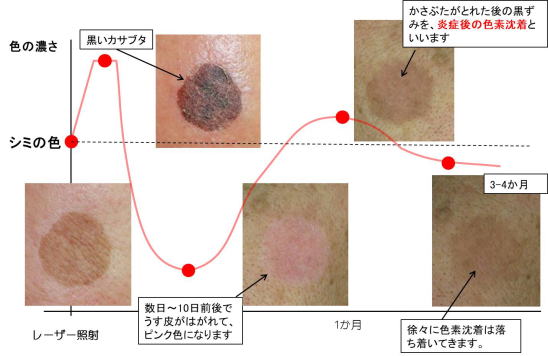

レーザーでシミ治療を行った1ヶ月後の経過 炎症後色素沈着- 東京・大阪の美容皮膚科ならFLALU フラルクリニック。

シミのレーザー治療後の経過・炎症後色素沈着を検証してみたBeauty Tuning Clinic。